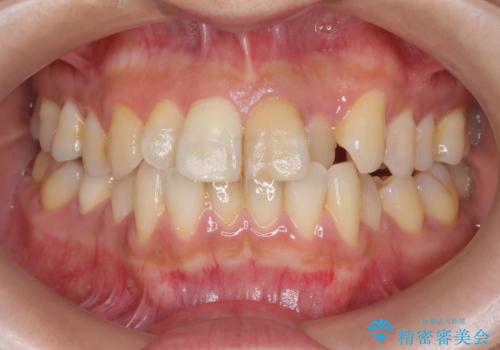

- 前歯の変色の改善を求めて来院されました。

根管内の感染は認められないのでセワミッククラウンの製作・装着を行い審美性を改善します。

- 13万円(仮歯・ファイバーコア・ジルコニアクラウンスタンダード)費用は治療当時の料金となります